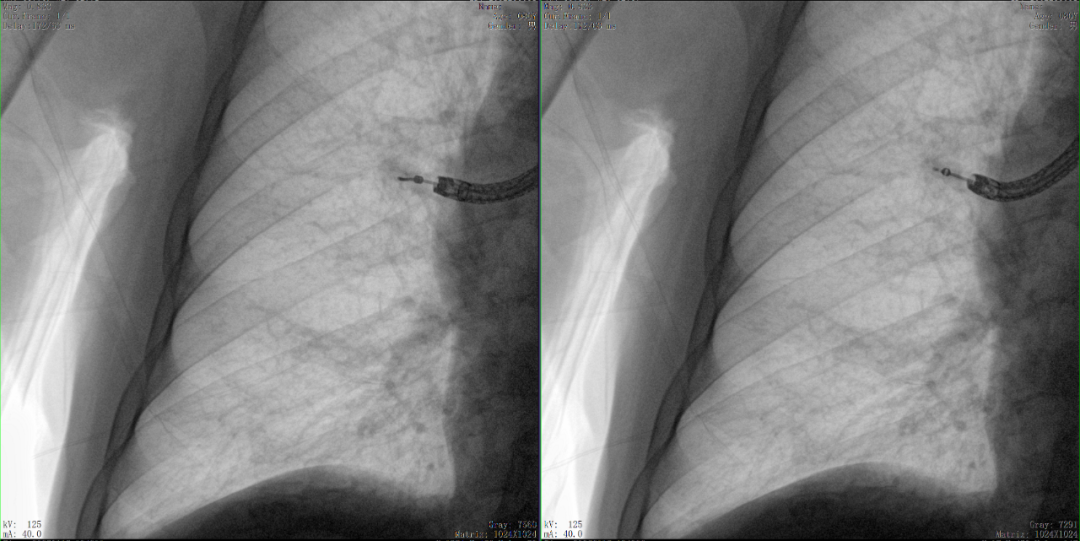

病例3:超声支气管镜下肺活检(80岁)

三维C形臂还可以创新性地应用在呼吸介入领域。例如,在经皮穿刺或经支气管镜肺结节活检、定位、消融等场景中,用于确认工具是否到达病灶、消融范围是否完全覆盖病灶等。

二维C形臂图像

二维影像无法准确判断工具是否到达病灶

三维C形臂图像

三维各切面影像都显示工具达到病灶内